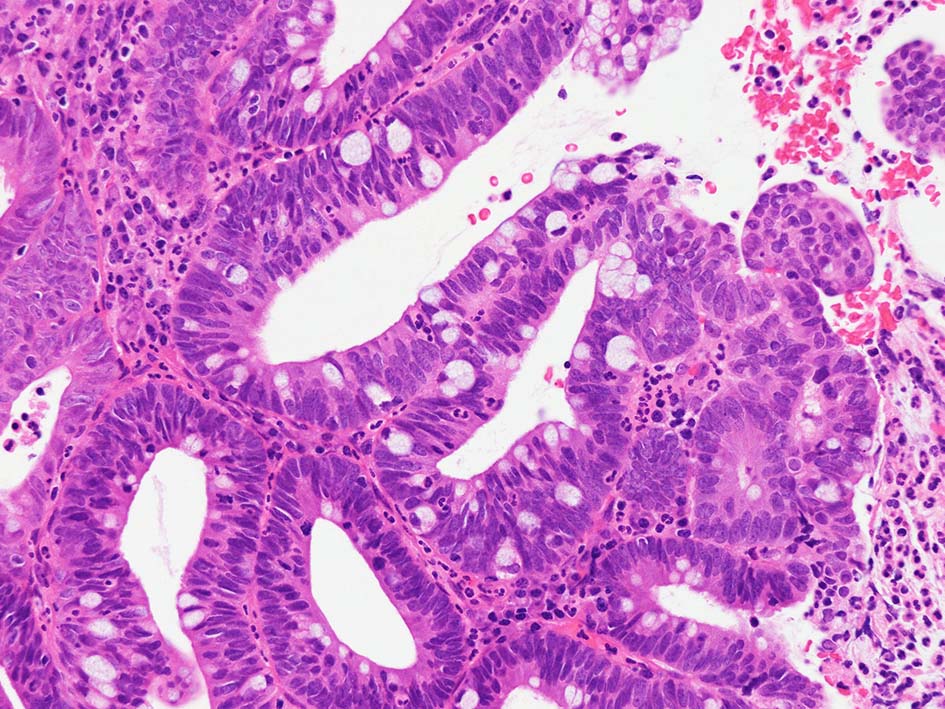

腸管型の腺癌。大腸の高分化腺癌と組織学的に区別は難しい.

neutrophilic exudate の付着する腸管型腺癌部分. 核はより腫大し円形、vesicularとなっている. 上記腸管型とはCK20, CK7のそまりが異なっていた. 変性のためかもしれない.